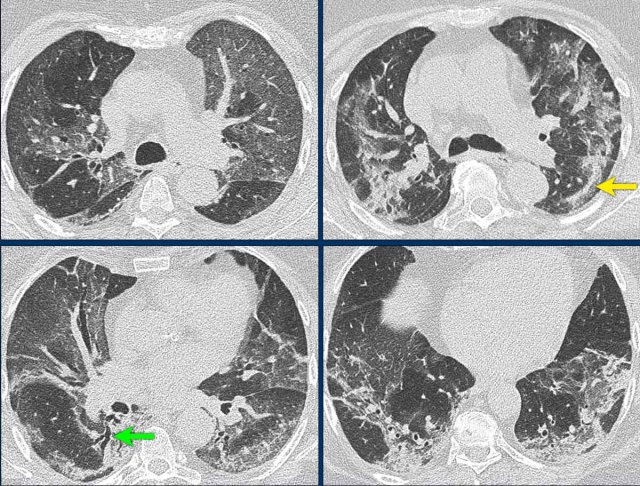

This patient had fever for one week with some abdominal pain and diarrhoea.

On the day of admission she had a dry cough and complained of dizziness.

The O2-saturation was low.

The PCR-test was not known and a CT was performed for triage.

The images show:

• Bilateral subpleural GGO's

• Consolidation in right lower lobe with traction bronchiectasis (green arrow).

• Fibrous bands (yellow arrow).

Based on the CT-findings COVID-19 infection was assumed to be highly likely - late phase.